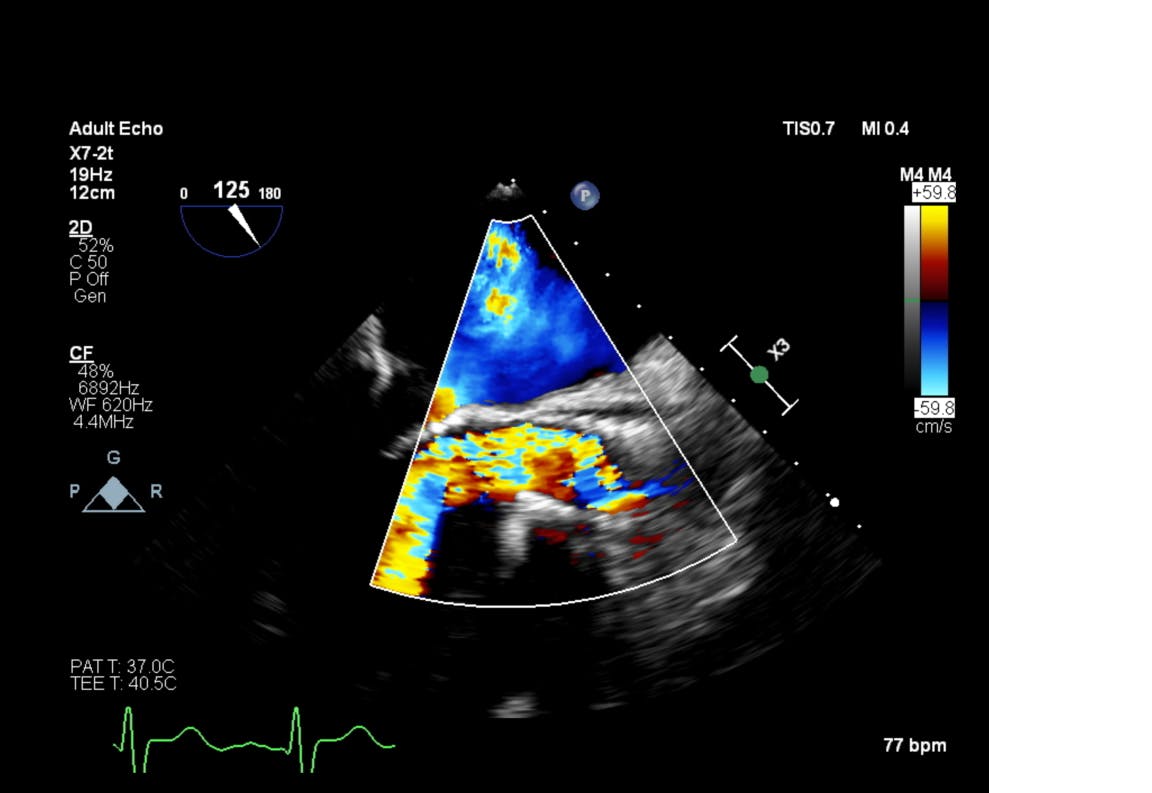

Procedura TAVI în TAVI a fost efectuată sub anestezie generală și ghidaj ecografic transesofagian, prin abord transfemural ceea ce presupune o puncție în artera femurală, localizată la rădăcina coapsei piciorului. După ce a fost efectuată puncția, medicii au introdus catetere speciale și au ghidat proteza valvulară în formă compactă până la nivelul protezei existente. Aici au efectuat măsurători pentru poziționarea exactă a dispozitivului și au efectuat manevre medicale pentru expandarea și fixarea acesteia.

Înainte de a fi externat, s-a efectuat ecografia cardiacă de control care a arătat că proteza aortică nou implantată funcționează normal. O veste extrem de bună pentru pacient care își poate relua activitățile zilnice, fără a mai obosi la cele mai mici eforturi.